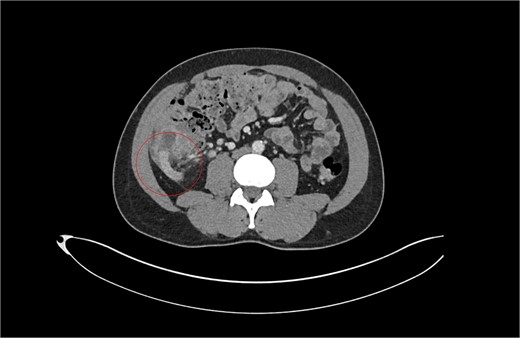

Review of previous notes revealed that the patient had a laparoscopic appendicectomy 2 years prior from a CT-confirmed acute retrocaecal appendicitis with localized perforation at the tip (Fig. 1). Intraoperatively, the dissection proved difficult due to the presence on multiple inflammatory adhesions and the retrocaecal position of the appendix, however a retrograde appendicectomy was completed laparoscopically. The postoperative period was complicated by a right iliac fossa abscess that was successfully treated with IV antibiotics and CT-guided drainage. The index histology revealed multiple pieces of appendiceal tissue aggregating to 60 mm × 40 mm × 20 mm, with acute inflammation and necrosis.

Patient A. Appendiceal stump of Patient A identified within the red circle on CT scan before the second operation.